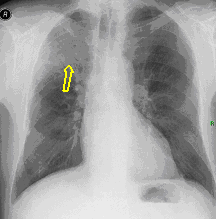

17a, b: Apical TB. HRCT, coronal reconstruction

Right apex, segment 1: reticular pattern and mosaic-like ground glass opacity (similarly mind changes in b. 6th segment, too). Extensive TB-specific lesions in apical dominance.